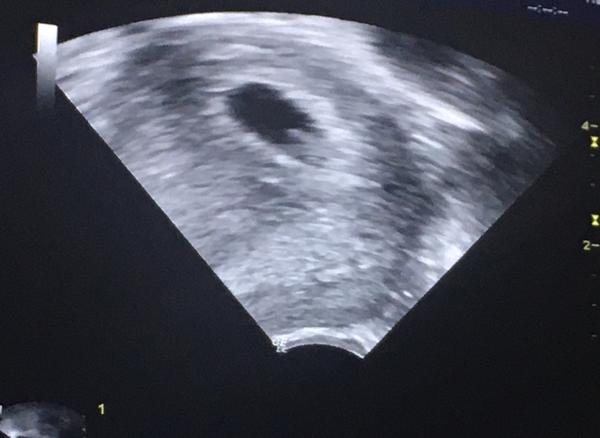

@fialka444 6+6 🙂 plod už vidět, 3mm, srdeční akce přítomna